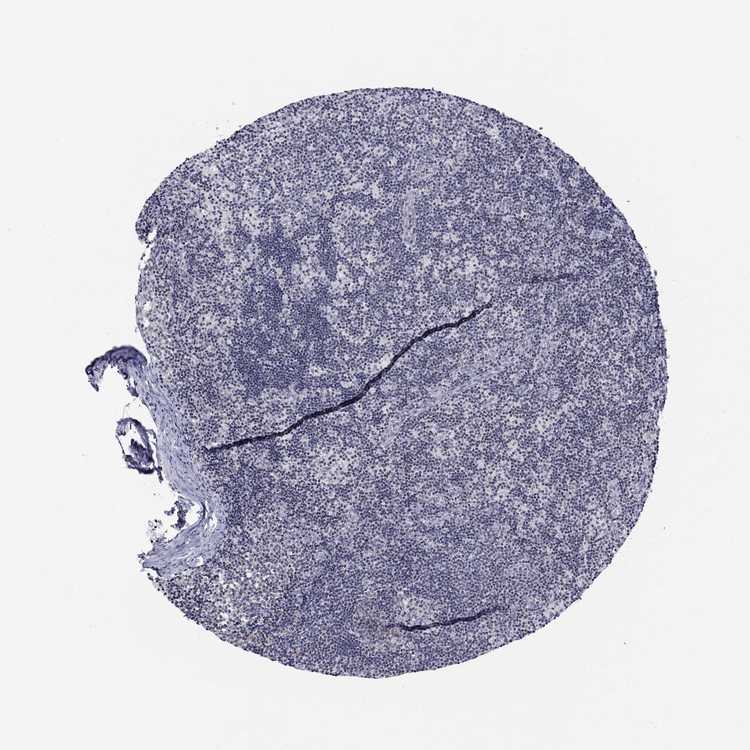

TISSUE PRIMARY DATA LYMPH NODE Show tissue menu

Lymph node

LYMPH NODE - Expression summary

LYMPH NODE - Antibody stainingi

Antibody staining in the annotated cell types in the current human tissue is reported as not detected, low, medium, or high, based on conventional immunohistochemistry profiling in selected tissues. This score is based on the combination of the staining intensity and fraction of stained cells.

Each image is clickable and will lead to virtual microscopy that enables deeper exploration of all samples and also displays staining intensity scores, fraction scores and subcellular localization as well as patient and tissue information for each sample.

Antibody HPA075652

Germinal center cells High

Non-germinal center cells Low